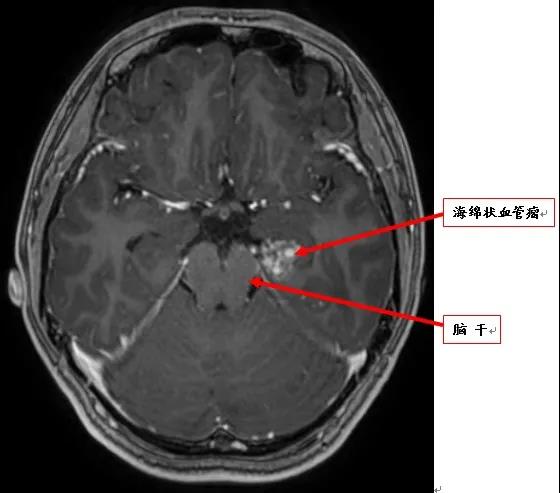

小李的父母慌了神,平时健健康康的孩子,怎么突然得了这种怪病?在当地医院进行颅脑核磁共振(MRI)检查发现左颞叶、脑干旁有一病变,考虑海绵状血管瘤。因部位比较特殊,手术难度大,风险高,当地医生建议口服药物控制病情。

术前MRI显示脑干有海绵状血管瘤

小李母亲几经辗转来到南方医科大学中西医结合医院神经外科寻求进一步治疗。入院后脑电图检查显示:左颞叶存在癫痫波形。神经外科主任陈陆馗认为,小李发病时的表现是癫痫的典型症状,而癫痫的罪魁祸首是左颞叶海绵状血管瘤

陈陆馗解释,海绵状血管瘤容易破裂出血,而小李颅内的海绵状血管瘤位于脑干旁,一旦出血,则血肿直接压迫脑干,会危及生命,必须尽快手术切除,以免贻误病情。完善术前准备后,2020年12月11日,在术中电生理监测下,陈陆馗为小李行海绵状血管瘤切除术,彻底切除海绵状血管瘤及与异常脑电波形有关的病变。